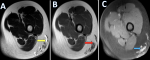

Figure 2: evolution of skin lesions in case 1; sequential evolution of skin lesions of acute hemorrhagic edema of infancy in case 1; A) extension of cockade-like purpuric plaques on the lower limb 24 hours after onset, with lesions extending beyond the initial marker outlines; B, C) progressive fading and near-complete resolution of the lesions by day 6